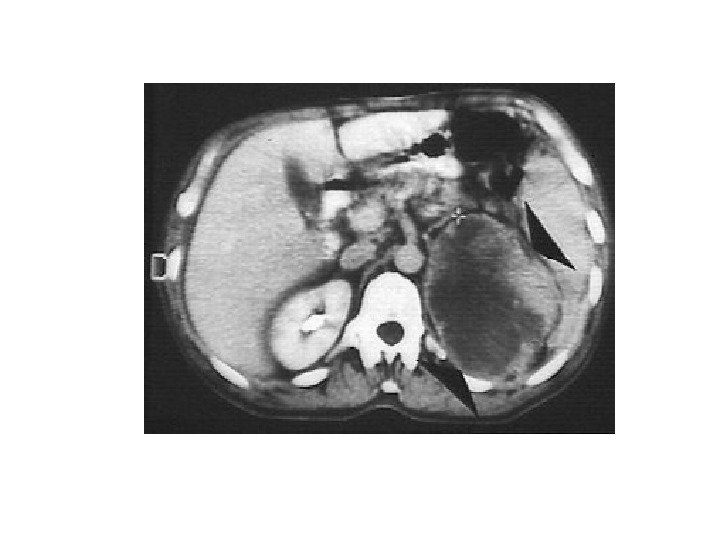

• В 10% случаев при феохромоцитоме компьютерная томография выявляет двустороннее поражение надпочечников. • Билатеральная феохромоцитома часто проявляется как незначительное увеличение надпочечников, с заметным повышением их васкуляризации. • Необходимо помнить, что феохромоцитома может иметь и вненадпочечниковую локализацию, располагаясь в паракавальных симпатических ганглиях, симпатических ганглиях средостения, ганглиях стенки мочевого пузыря.

• В 10% случаев при феохромоцитоме компьютерная томография выявляет двустороннее поражение надпочечников. • Билатеральная феохромоцитома часто проявляется как незначительное увеличение надпочечников, с заметным повышением их васкуляризации. • Необходимо помнить, что феохромоцитома может иметь и вненадпочечниковую локализацию, располагаясь в паракавальных симпатических ганглиях, симпатических ганглиях средостения, ганглиях стенки мочевого пузыря.